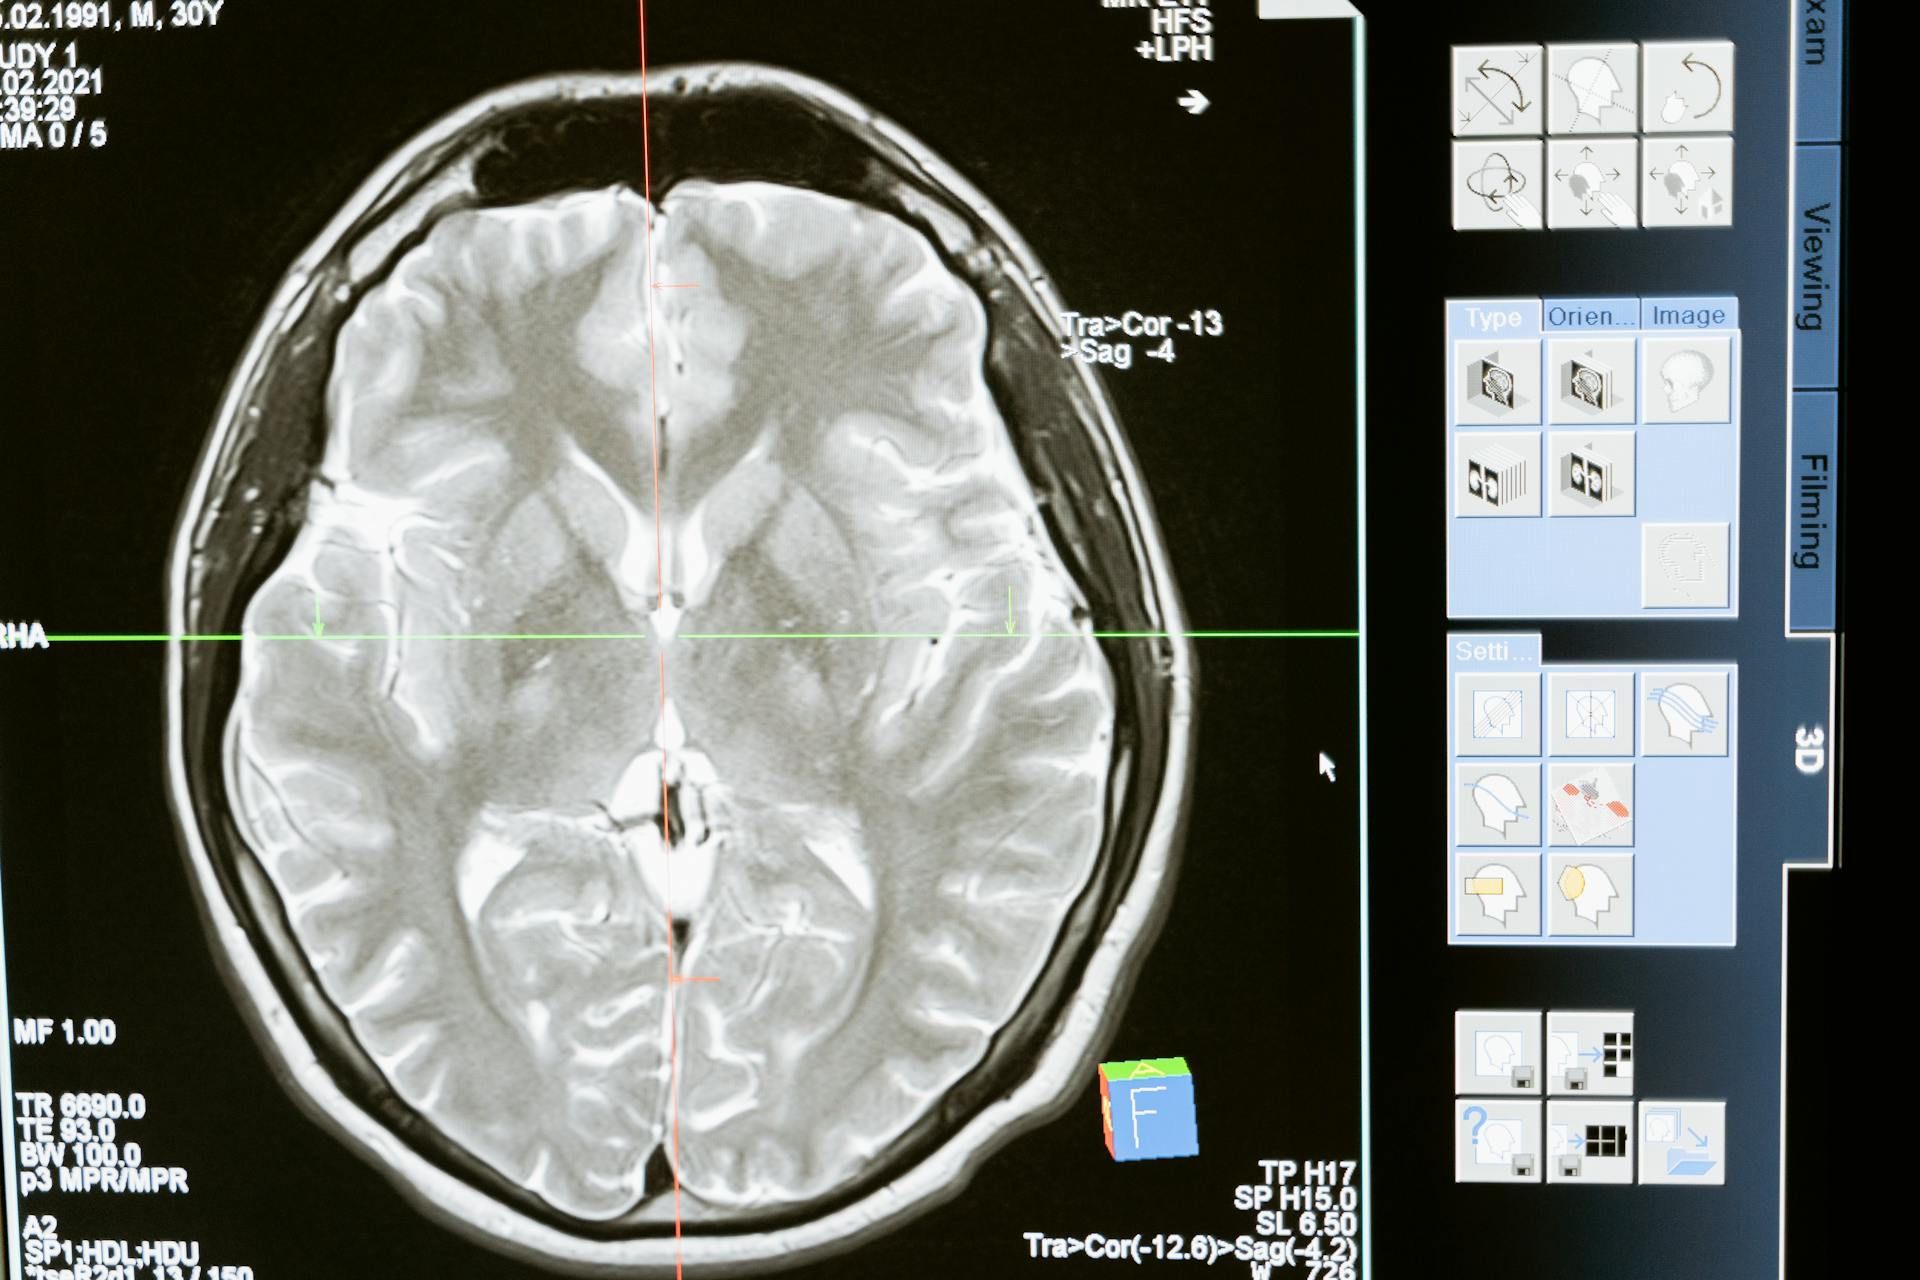

Транзиторная ишемическая атака (ТИА) обнаруживается на МРТ не более суток, а ее симптомы обычно длятся не более часа. Если ишемия сохраняется дольше, это свидетельствует о развитии ишемического инсульта. Симптомы обоих состояний могут быть похожими, разница только в продолжительности патологических изменений.